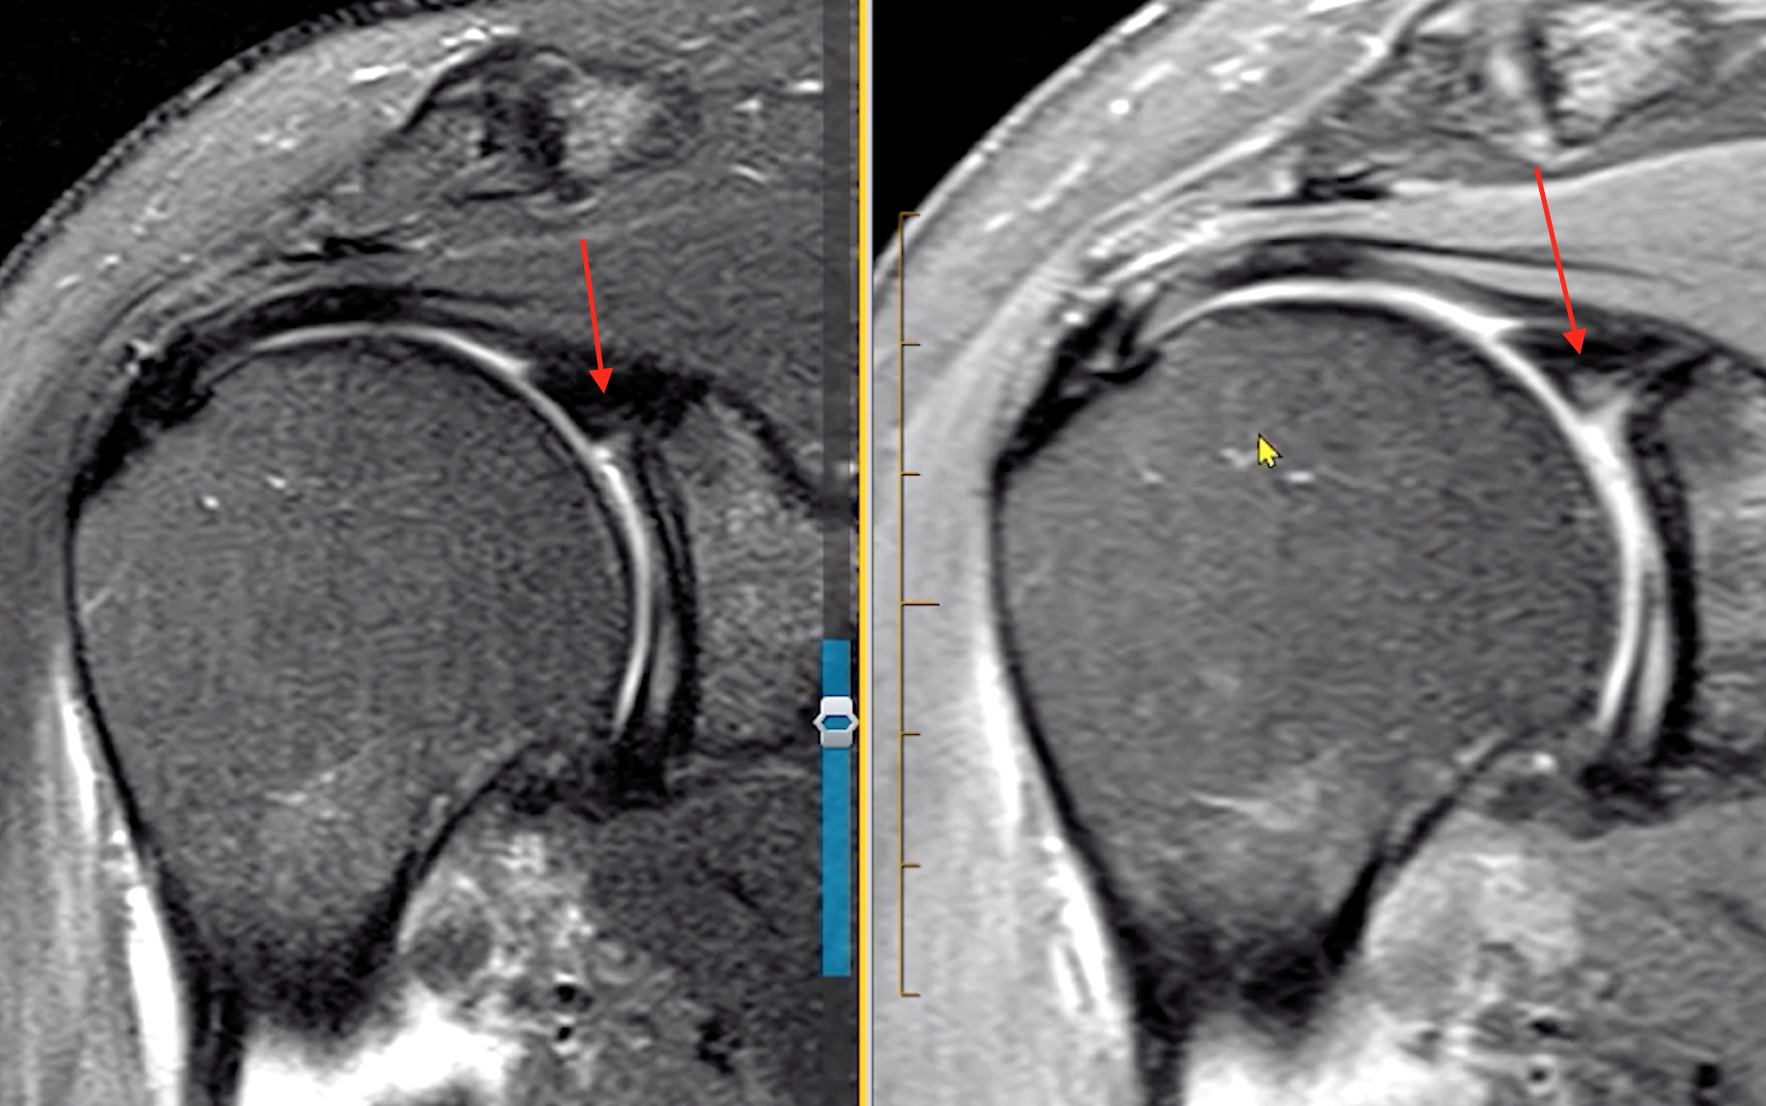

Adhesive Capsulitis

• Capsule thickening and edema

• IGHL ligament thickening, typically >4 mm

• Soft tissue thickening of the rotator cuff interval

• Loss of fat here

• T2 hyperintense & enhance

• Coracohumeral ligament thickening (> 4mm)

• Decreased capsular volume

• Axillary recess appears small

• Basically no fluid around shoulder and the tissues adhere close to the humerus bone

• Unless concurrent other shit the rotator cuff itself and labrum are normal